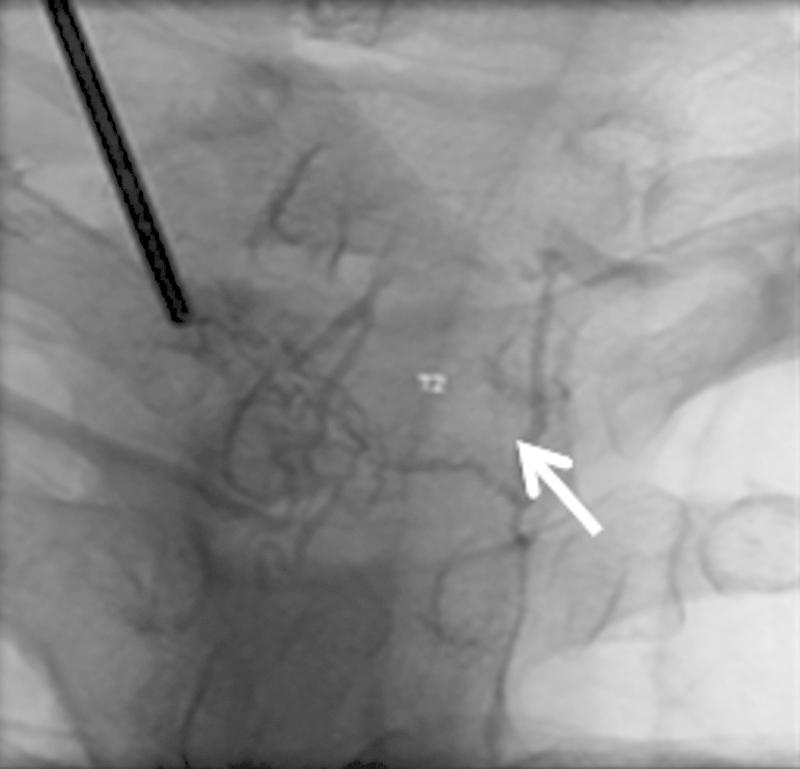

Vertebral hemangiomas are benign lesions accounting for 2 to 3% of all spinal tumors. They are usually asymptomatic and found incidentally on imaging. Uncommonly, vertebral hemangiomas with significant epidural extension can result in radiculopathy or spinal cord compression. Decompressive surgery with or without stabilization is often required when neurological deficits are present. However, surgery can be associated with massive hemorrhage as these tumors are hypervascular. Preoperative embolization and sclerotherapy are well-known management strategies used to minimize intraoperative bleeding and improve symptoms. Recently, the use of sclerosants such as ethanol has decreased, due to reported complications such as Brown-Sequard syndrome. We describe the use of sodium tetradecyl sulfate (Fibro-Vein™, STD Pharmaceutical, Hereford, UK) as an effective alternative to ethanol in the preoperative management of vertebral hemangiomas. To our knowledge, this has not been previously reported. In three patients, we demonstrated minimal intraoperative blood loss using a combination of preoperative embolization of arterial feeders and sclerotherapy with sodium tetradecyl sulfate to control and secure venous drainage. No patients developed complications related to the procedure. In addition to minimal blood loss, a clear dissection plane was also noted intraoperatively.